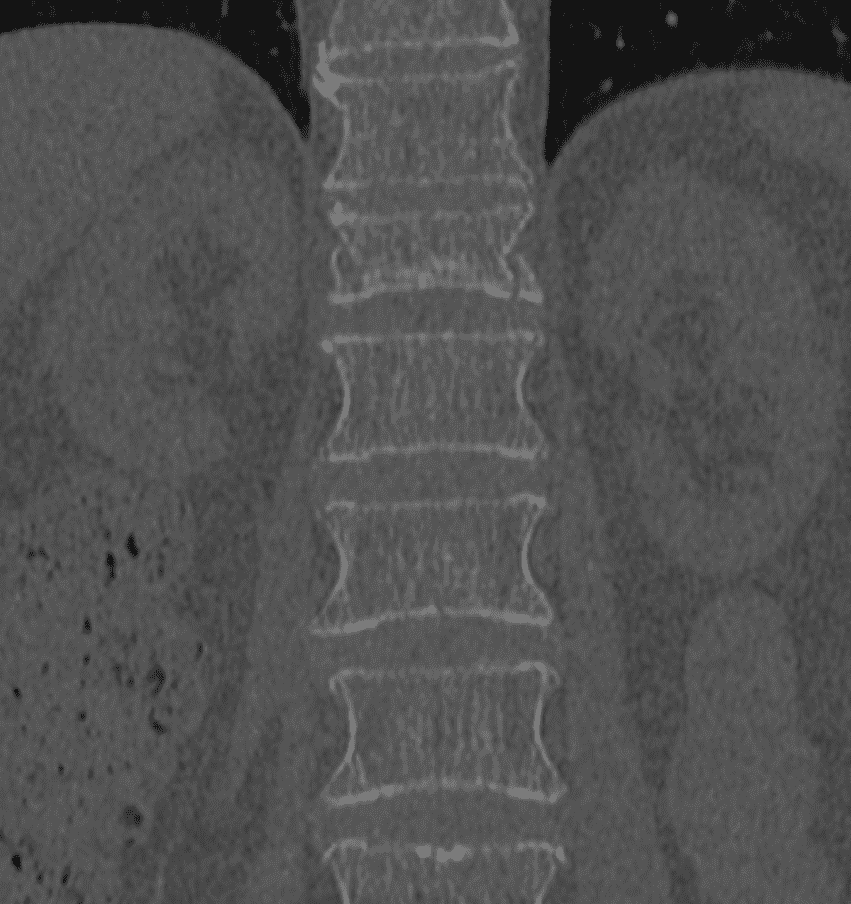

Guidage par imagerie

À l’aide de la fluoroscopie et/ou du scanner, l’équipe médicale guide avec précision une aiguille jusqu’au site de la fracture, en s’assurant d’éviter les structures sensibles.

L’implant SPINEJACK est une technique de radiologie interventionnelle, innovante et peu invasive, qui offre une alternative aux méthodes traditionnelles telles que la vertébroplastie ou la kyphoplastie. Cette procédure consiste à insérer un implant métallique à l’intérieur de la vertèbre fracturée. Une fois positionné, l’implant est déployé pour restaurer la hauteur et la forme normale de la vertèbre, ce qui aide à réaligner la colonne et à réduire la compression sur les structures nerveuses. Par la suite, un ciment osseux est injecté pour consolider l’implant et stabiliser la fracture.